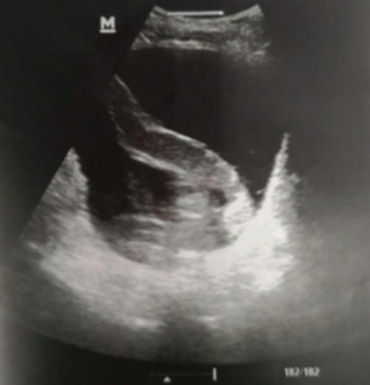

НемедицинаFigure 1. Ультразвуковое исследование показывает трубчатую структуру мочевого пузыря, которая, вероятно, является пиявкой